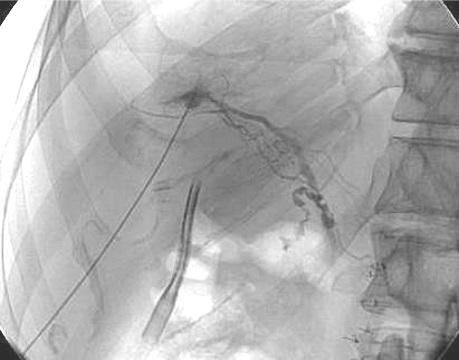

Liver Lymphangiogram PLE

假设蛋白丢失肠病中的蛋白丢失是由于肝淋巴漏到肠道 Liver Lymph Production

肝淋巴系统解剖